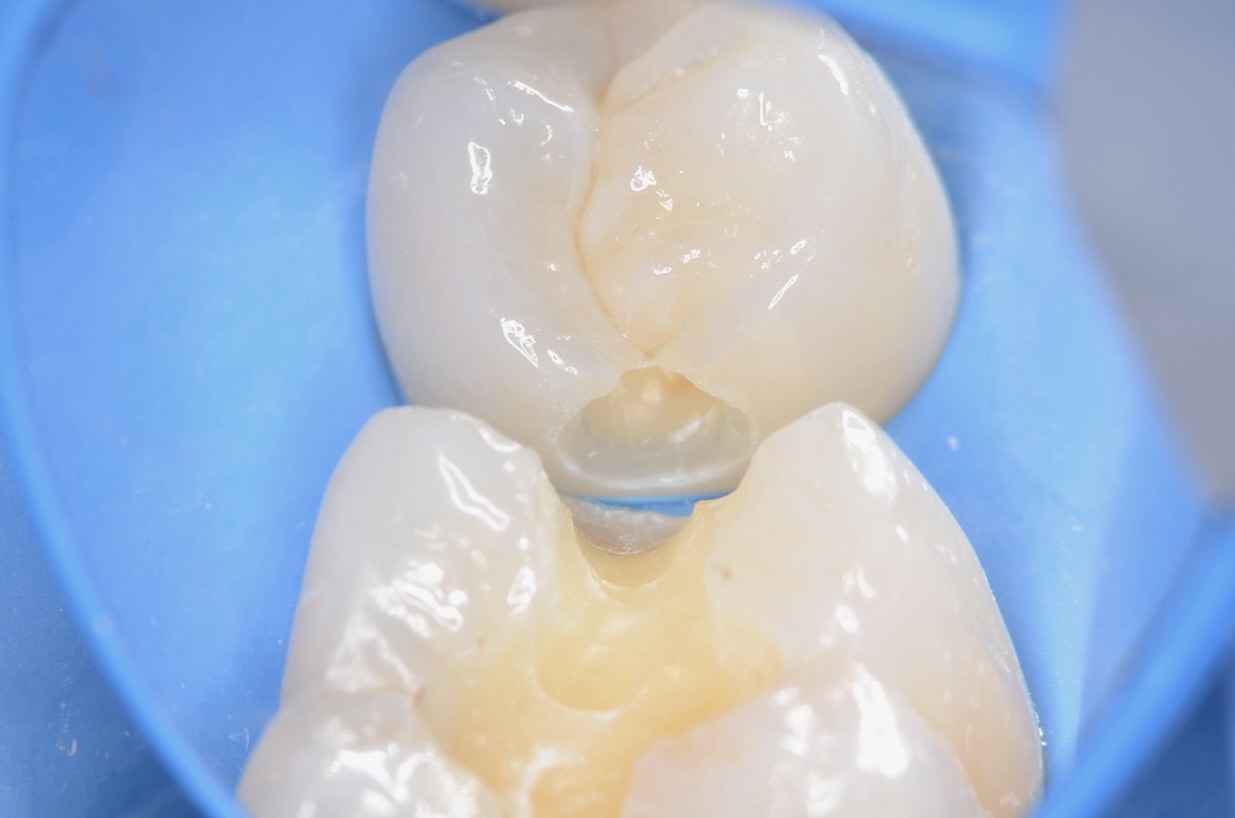

ジルコニアインレーの接着操作

唾液や血液から歯面が汚染されるのを防ぎ、乾燥状態を保つラバーダムは、接着力を向上させるためにも大切なアイテムです。 接着剤が隣の歯にかからないようにテープで養生します。 -

レジンセメント硬化

ジルコニアインレーを光硬化型のレジンセメントにて接着します。 -